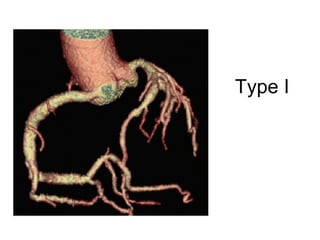

Markis JE. Am J Cardiol 1976;37(2):217

Type I

Ectasia Markis JE.Am J Cardiol 1976;37(2):217